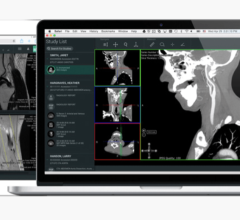

These two prototype “proof of concept” awards reportedly provided new ways for clinicians to expand usability of CT and MR volumetric data sets and to be able to use that flexibility to communicate and share information throughout the radiology informatics environment. Physicians from the University of Maryland and VA Baltimore worked with TeraRecon engineering to develop these award-winning exhibits.

The first award exhibit, was entitled, A Truly Clientless AJAX-based 3D Image Viewer for MIRC Based on an IHE-TCE-Compliant 3D Client-Server Solution. This winning exhibit featured the AquariusWEB viewer, which was embedded seamlessly into the RSNA Medical Imaging Resource Center (MIRC) project for managing image-based teaching files for educational and research purposes.

The second award exhibit was entitled, Novel Uses of the Nintendo Wii Remote in the Navigation of Multidetector CT Datasets. In this instance, the Wii-mote was used as an alternative to traditional mouse-based input, to manipulate and review volumetric CT data. The flexibility of holding the Wii-mote in the hand removes the structured boundaries of a normal mouse and allows the user to remove the learning curve sometimes needed to manipulate a PC mouse.

Another exhibit utilized a “Multi-Touch” display to navigate volumetric CT and MR datasets. This technology allows users to manipulate data directly with their fingers through a touch screen and promises to remove the learning curve and constraints of a traditional mouse or trackball, icons and pull down menus.